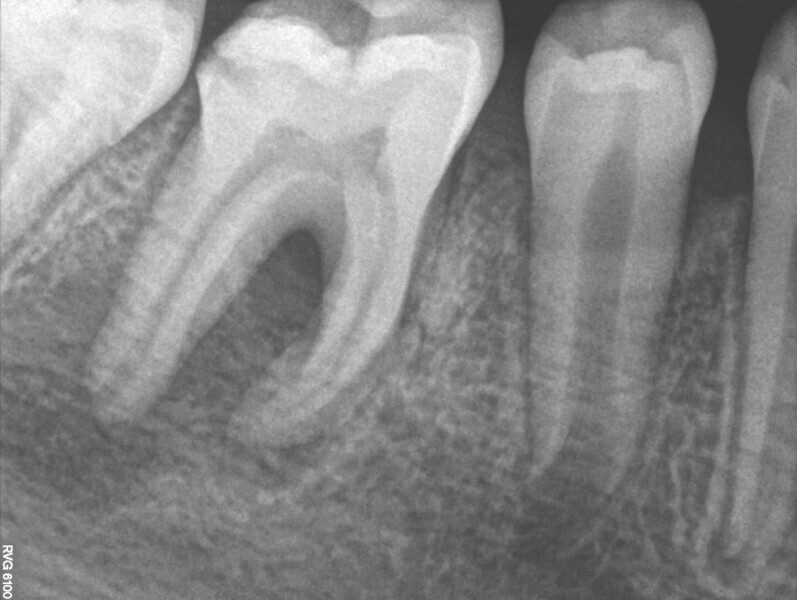

Fig. 3: Pre-op radiograph of tooth #46 showed a large area affected by periapical periodontitis going up into the furcation.